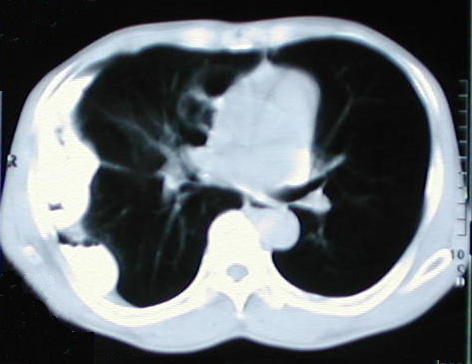

• Una radiografía torácica anormal, en octubre del 1999, reportada inicialmente como reacción pleural de tipo residual, en evaluación traumatológica por disfunción de la articulación del tobillo izquierdo sugiere evaluación neumonológica, los nuevos estudios radiológicos del tórax demuestran patología caracterizada radiopacidad basal derecha con borramiento del hemi diafragma e imágenes de aspecto hidroaereo que plantea la posibilidad de una hernia diafragmática de contenido gastrointestinal de probable etiología pos traumática.

• Puede observarse en los estudios, la hiperplasia funcional compensatoria del pulmón Izquierdo

También puede observarse la hiperplasia compensatoria del pulmón Izquierdo.